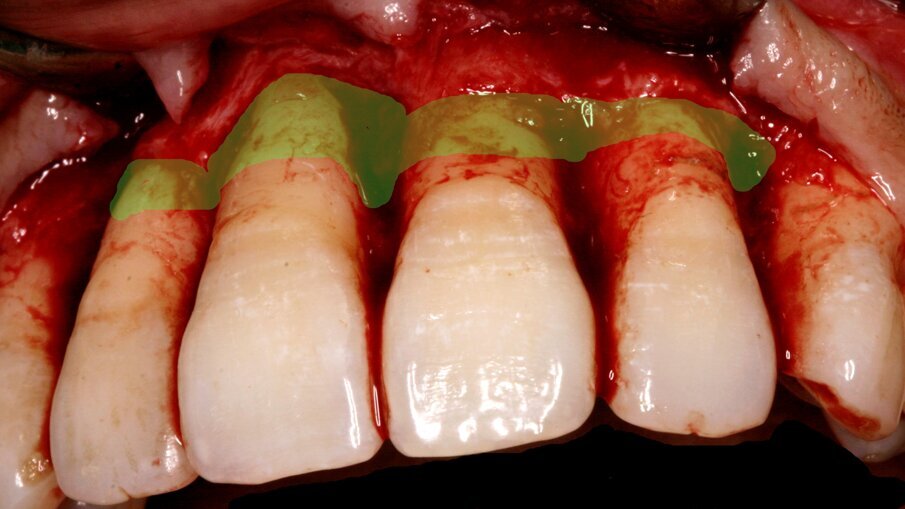

Before surgery, all participants received phase I periodontal therapy. During the surgical procedure, a full-thickness flap was reflected to expose the affected teeth. In Group A, DBBM was placed on the buccal side of the teeth and covered with a collagen membrane, while Group B only underwent debridement. Post-surgery, all patients were provided with antibiotics and pain relief medication to aid in their recovery.

Fig.3: Membrane placed and stabilized